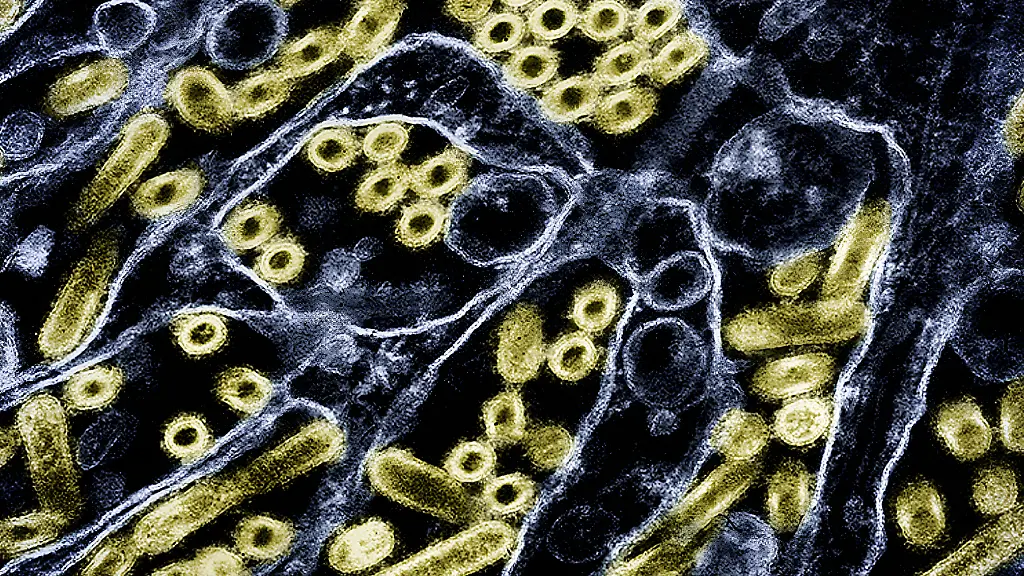

Ein Infektionsfall auf einem kleinen Bauernhof im US-Bundesstaat Oregon sorgt derzeit für Aufsehen. Dort wurde das Vogelgrippevirus H5N1 erstmals bei einem Schwein nachgewiesen, wie die zuständige US-Landwirtschaftsbehörde USDA mitteilte. Es hatte sich offenbar bei infizierten Hühnern angesteckt. Gewebetests ergaben, dass das Schwein "im ganzen Körper Viren hatte", sagte Ryan Scholz, der staatliche Tierarzt von Oregon, dem US-Online-Portal "Statnews".

Dass nun nach Milchkühen auch ein Schwein betroffen ist, versetzt Fachleute in Alarmbereitschaft. Schweine werden manchmal als "Mischgefäß" für Grippeviren bezeichnet, da sie sich gleichzeitig mit Vogelgrippeviren und auch menschlichen Grippeviren infizieren können. Durch den Austausch von Genen kann dann ein neues, gefährlicheres Hybridvirus entstehen, das den Menschen leichter infiziert. Eine Mensch-zu-Mensch-Übertragung von H5N1 wird wahrscheinlicher.

Früheren Studien zufolge können H5N1-Viren Schweine zwar infizieren, sich aber nicht besonders gut unter ihnen verbreiten. Mit den neuen Varianten könnte sich das jedoch ändern. Eine aktuelle Untersuchung von Wissenschaftlern des US-Landwirtschaftsministeriums ergab, dass die Vogelgrippe-Variante, die derzeit in den USA zirkuliert, Schweine deutlich leichter infizieren könne.